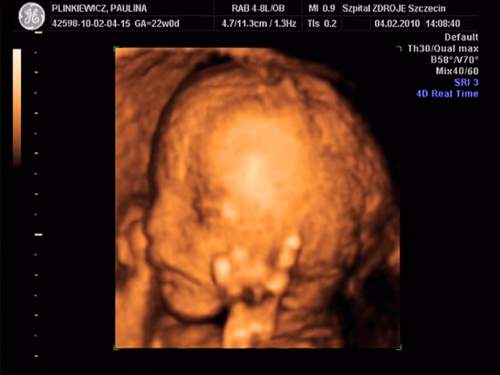

MAleńka jest super....Rozumiem że to imienniczka mojej córci - Pola!!!! Jest cudowna...Gratuluję!!!!Moja córeczka:

na drugim zdjęciu ziewa :-) a na ostatnim trzyma się za uszko:-)